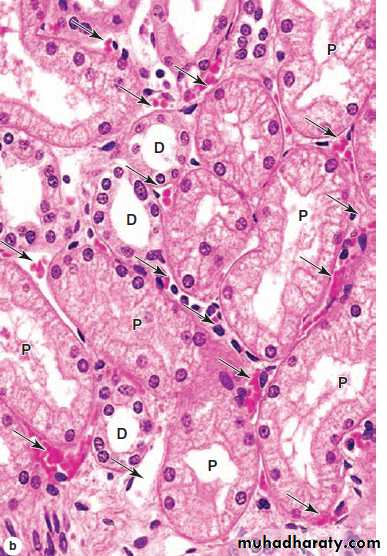

Renal Cortex Proximal and distal convoluted tubule